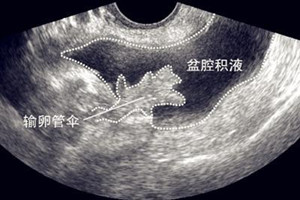

由于盆腔位于腹腔最低位置,当有渗出液或漏出液时都会引流到盆腔,从而型成盆腔积液。部分女性在月经期或排卵期会有少量血液从输卵管渗出,输卵管呈伞形,如果输卵管没有堵塞,渗出的少量血液会到达盆腔,从而形成盆腔积液。

B超检查是发现盆腔积液最有力的手段之一

一般认为超过1cm的积液就是异常积液,即病理性。通过B超检查,还可以看到液体的性质及盆腔脏器的情况,对渗出物进行初步的判断。如盆腔大量积液内透声差,就说明是炎症所引起的病理性积液,要及时治疗。